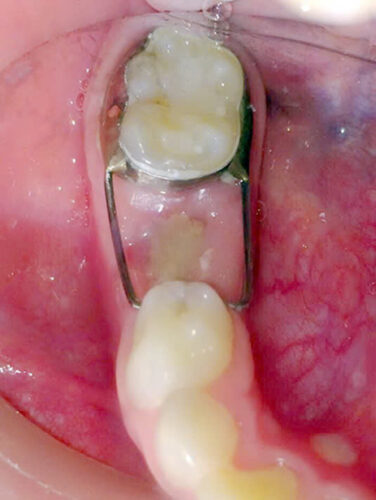

Hàm giữ khoảng Distal Shoe khi mất răng 5 sữa sớm, răng 6 vĩnh viễn chưa mọc

Hàm giữ khoảng Distal Shoe